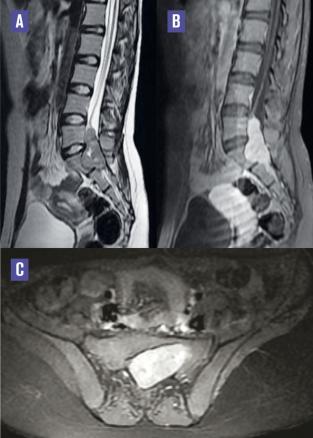

Cette patiente de 20 ans avait, depuis 6 mois, une lombosciatalgie d’installation progressive (territoire de la racine nerveuse S1 gauche) avec apparition de troubles sphinctériens. L’examen notait une parésie et une hypoesthésie avec un niveau sensitif et des réflexes ostéotendineux vifs du membre inférieur gauche. L’IRM lombosacrée ( v. figure) en coupe sagittale T2 montrait une lésion tissulaire en regard de L5 et S1, bien limitée en isosignal T2, un discret hypersignal T1 réhaussé intensément après injection du produit de contraste et étendu à l’espace épidural à travers le foramen de conjugaison de L5-S1 (avec son élargissement), et une compression des racines de la queue de cheval, évoquant un neurinome ou un hémangiome capillaire épidural. Une hémilaminectomie gauche était réalisée avec exérèse en bloc du processus épidural dont l’anatomopathologie était en faveur d’un hémangiome capillaire épidural lombosacré. La patiente était rapidement soulagée, se levant 24 heures après l’intervention et récupérant des troubles génitosphintériens.

Les hémangiomes capillaires, très rares, sont des proliférations harmatomateuses des cellules de l’endothélium vasculaire.1, 2 L’hémangiome capillaire épidural est plus souvent localisé au niveau du rachis dorsal.1, 2 Nous rapportons le 2e cas de localisation lombosacrée. Il se manifeste par un syndrome rachidien, une radiculalgie, ou une myélopathie chronique dus à un effet de masse sur la moelle ou les racines. L’IRM est l’examen clé du diagnostic, mais l’aspect de l’hémangiome capillaire épidural est non spécifique.1 Elle montre une image bien limitée, parfois en sablier, posant un problème de diagnostic différentiel avec le neurinome et le méningiome. La présence d’un drainage veineux, défini comme un vide vasculaire à l’IRM, témoignerait du caractère hypervascularisé de la lésion et permettrait de faire la différence avec les autres tumeurs solides. Le traitement consiste en une exérèse chirurgicale totale. Le pronostic de l’hémangiome capillaire épidural est favorable et aucun cas de récidive n’a été rapporté.